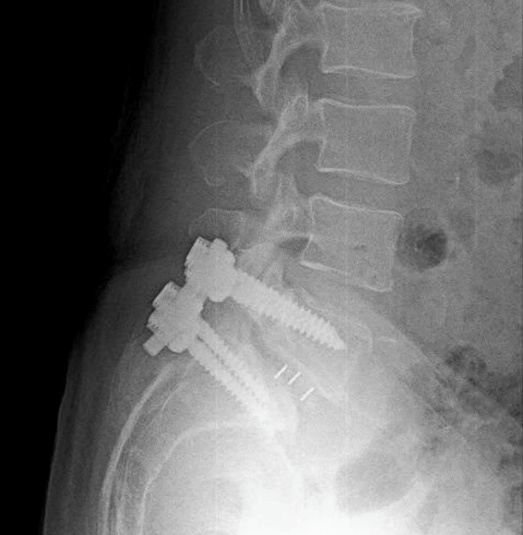

2.3. Điều trị bệnh lý cột sống: với sự hỗ trợ chuyên môn của Bệnh viện Chợ Rẫy, Bệnh viện Nhân Dân 115 TpHCM, Khoa đã và đang thực hiện phẫu thuật các trường hợp bệnh lý cột sống thắt lưng như: gãy cột sống; lấy nhân đệm thoát vị đơn thuần, qua kính vi phẫu; phẫu thuật trượt đốt sống; bơm xi-măng điều trị xẹp đốt sống do loãng xương;…Điều trị nội ngoại khoa các trường hợp Viêm thân sống đĩa đệm.

Phẫu thuật Trượt đốt sống L5S1